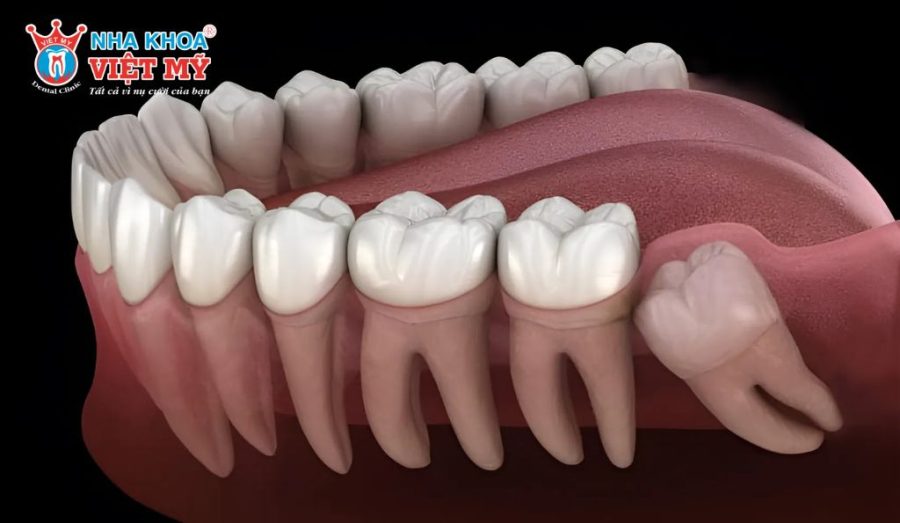

- Răng khôn mọc lệch, mọc ngầm gây đau nhức, sưng nướu hoặc đẩy các răng bên cạnh làm sai lệch khớp cắn.

Răng khôn mọc thẳng, chân răng đơn giản thường được nhổ dễ dàng, ít xâm lấn mô mềm và xương hàm nên vết thương sẽ hồi phục nhanh. Ngược lại, các trường hợp răng khôn mọc lệch, mọc ngầm hoặc có nhiều chân răng cong, gãy phức tạp sẽ khiến thủ thuật khó khăn hơn, đồng nghĩa với việc thời gian lành thương kéo dài.